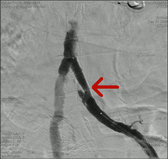

可怕的LEADDP 糖尿病下肢血管病变(LEADDP)可致患者肢体麻木、疼痛,间歇性跛行,乃至坏疽(糖尿病足),截肢率高达40 %以上。LEADDP是糖尿病致残、致死的主要原因,糖尿病患者因LEADDP造成的截肢,要比非糖尿病患者高5到10倍以上。先进的DSA + 微创介入 1、选择性血管造影(DSA)是LEADDP诊断的金标准。 2、微创介入治疗优点: 创伤小,仅有一2-3 mm的穿刺创口 成功率高:目前其成功率达85-90 % 保肢率高:术后病人截肢率可从40 %降为4 %左右 早发现早治疗:越早治疗效果越好.独创的微创介入 + HBO + bFGF综合治疗途径 1、DSA + 微创介入 2、高压氧(HBO)物理疗法:大型空气加压舱,治疗压力0.2 MPa,面罩吸纯氧30 min 3、基于重组成纤维细胞生长因子(bFGF)局部换药.